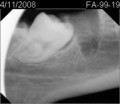

• D6A7C4F4-AA3C-4C45-80AB-887F7AC6034D.jpeg

D6A7C4F4-AA3C-4C45-80AB-887F7AC6034D.jpeg

10.5 KB · Views: 3